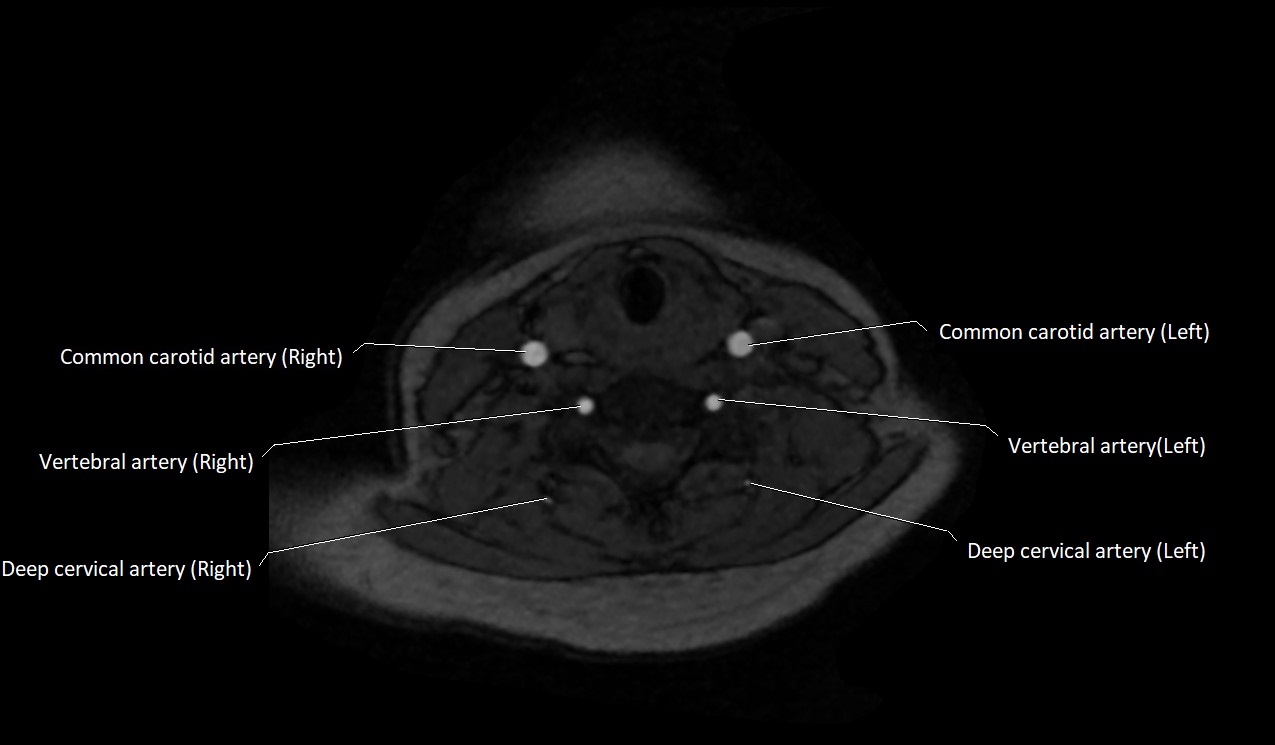

MRI images

image